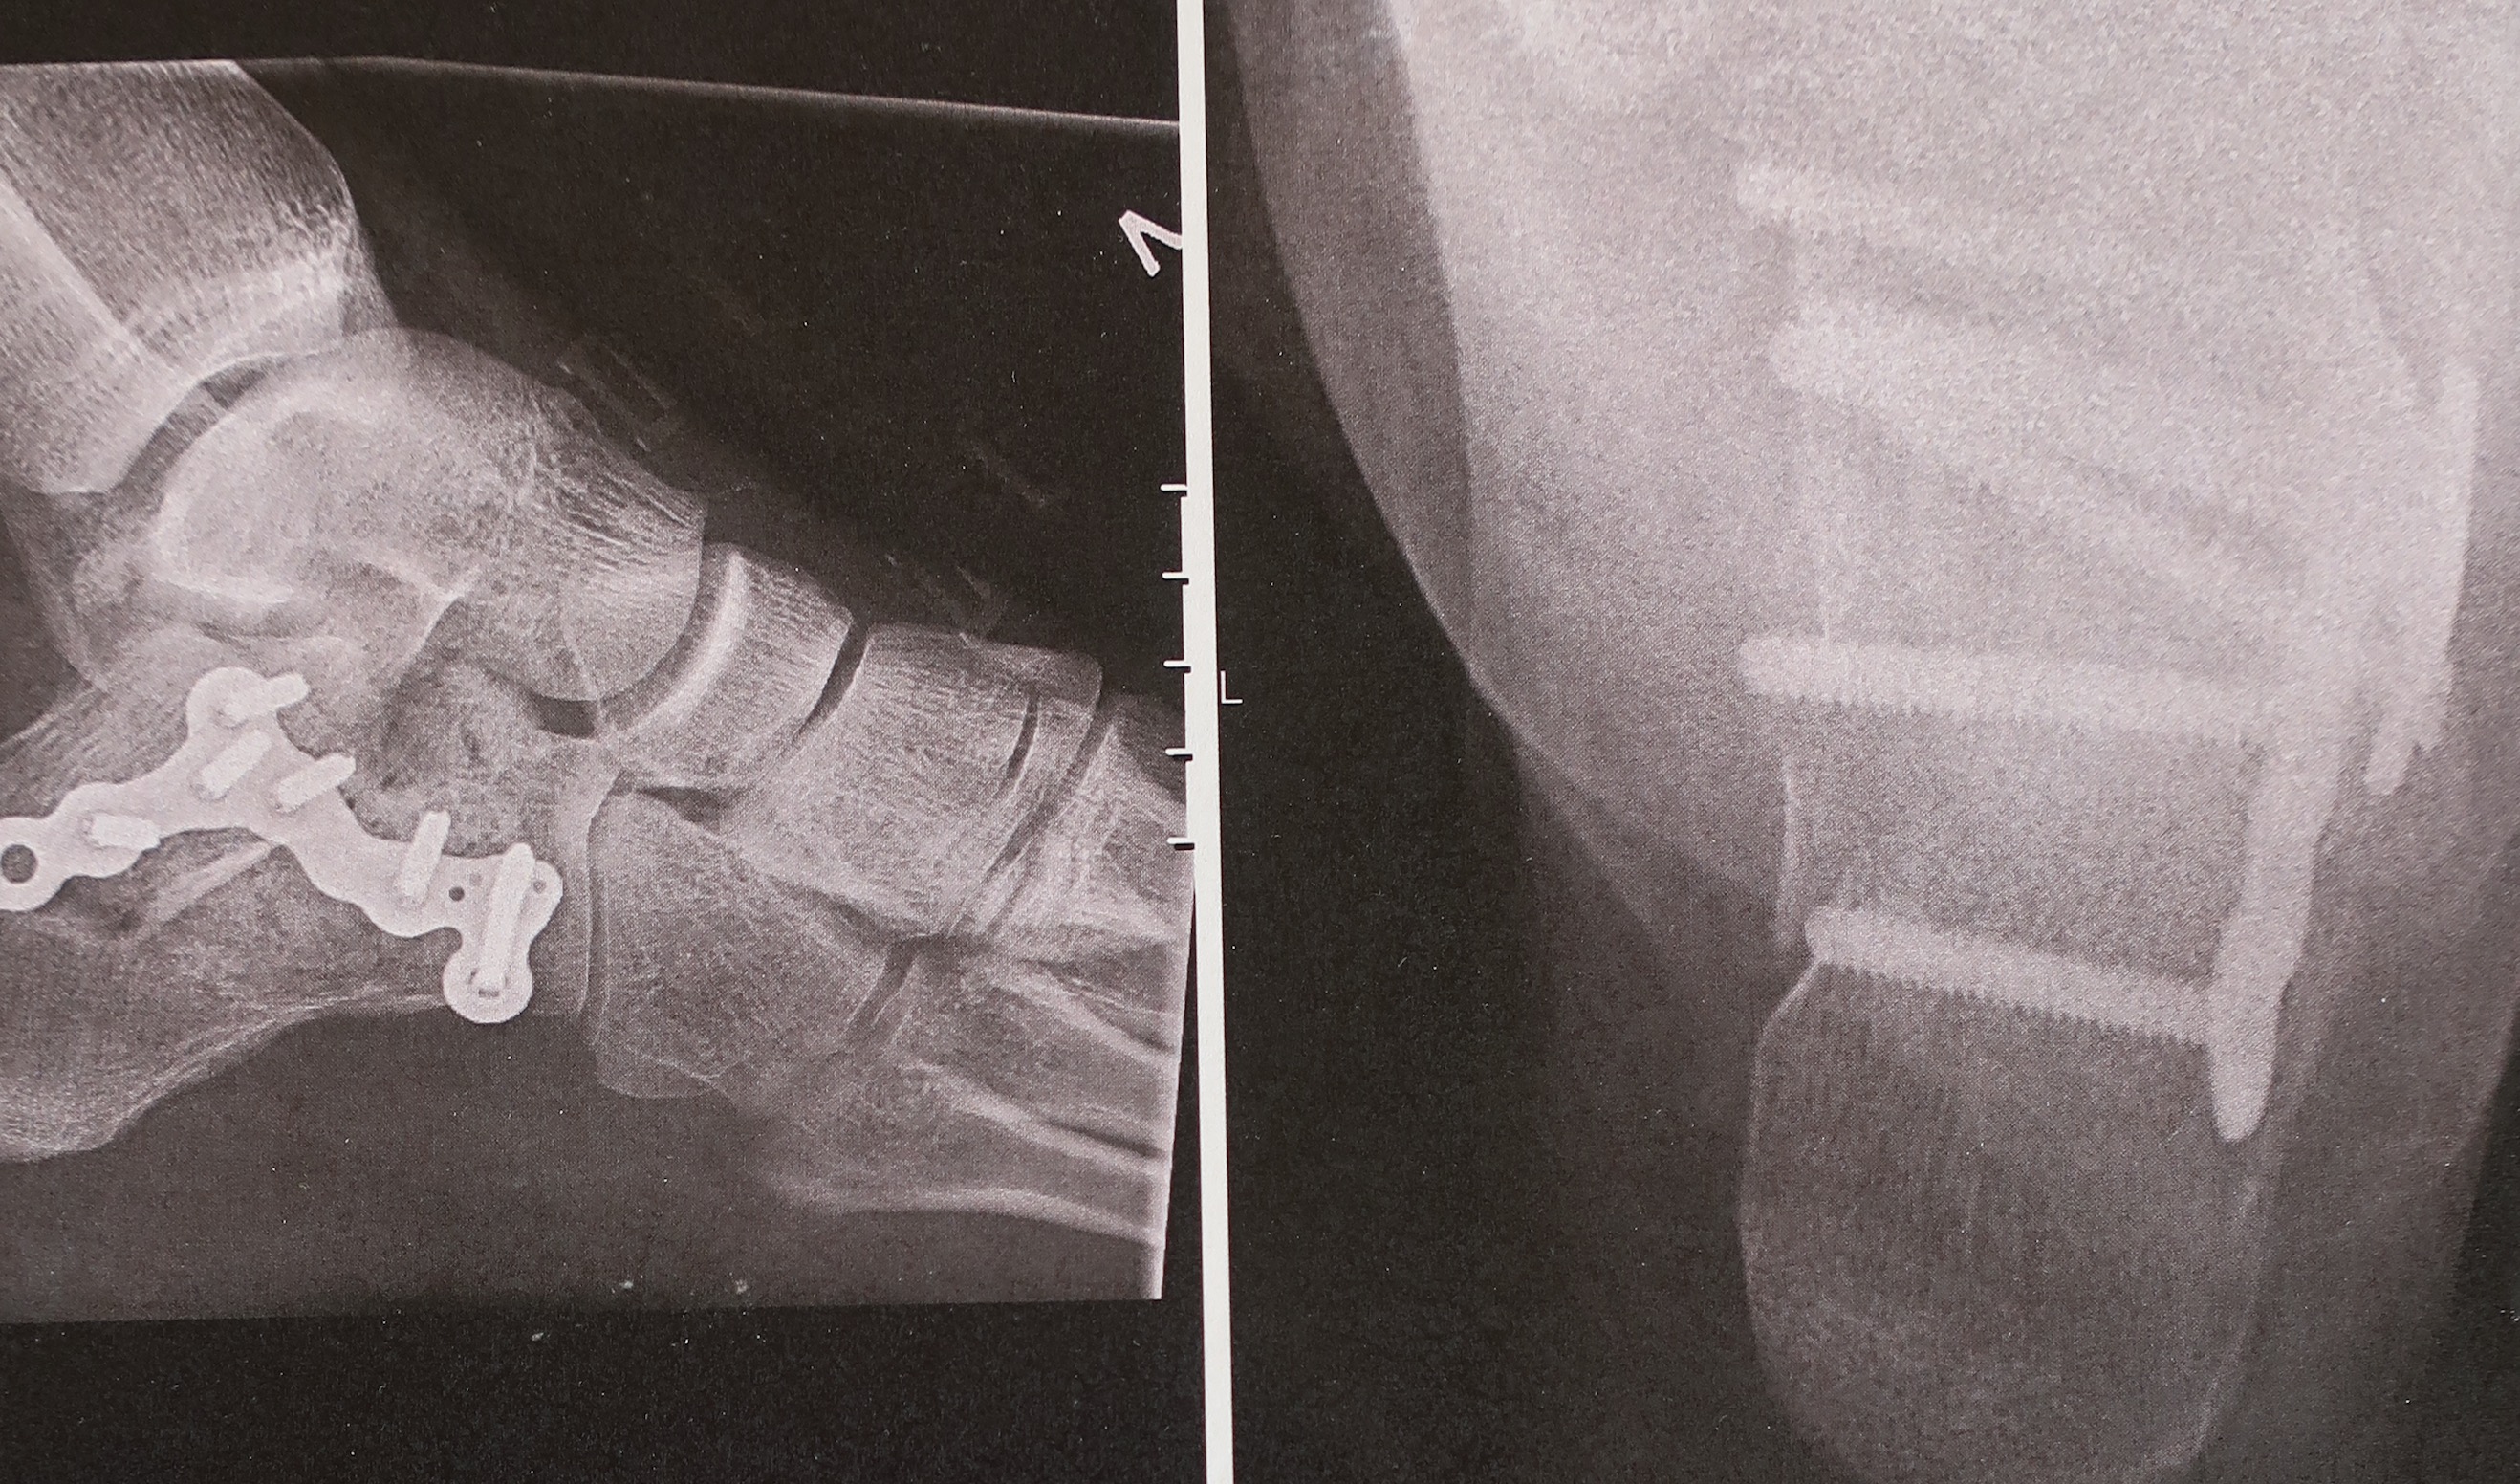

Vel nede på bakken er det klart at det ikke bare er brudd i foten, men et åpent brudd. En liten spile av blod – lik den tynne vannstrålen fra et lite hull i hageslangen – står ut fra siden av hælen. Bare å komme seg til sykehus. Med støtte fra sikreren og en klippestang som stokk får jeg hinket, hoppet, bakset og akt meg ned steinrøysa de to hundre meterne ned til bilen. En time og 17,5 mg morfin senere viser røntgenbildene at hælbeinet er fullstendig knust. Denne høsten blir annerledes enn planlagt.

Martin mister festet, og begynner å dels skli, dels falle ned svaet. Fallet blir til slutt 10-15 meter langt, og på veien har foten hans slått hardt borti et framspring. Smertene er heftige, men de amerikanske legene mener det ikke er snakk om brudd. Martin innser imidlertid selv at han er så skadet at han må komme seg hjem til Norge. På legevakta i Oslo får han konstatert et alvorlig hælbeinsbrudd – hælen er knust i 13 biter.

Mer overraskende er det at fallet ikke blir mykt og elastisk, men tvert imot hardt og kontant. Ole lander skjevt inn mot veggen og får en skikkelig smell i venstrefoten under landingen. Med isspray på foten, sikreren som støtte og klippestanga som stokk hinker han seg møysommelig den lange veien tilbake til parkeringsplassen og videre til legevakta. Der kan legene konstatere at talusbeinet i ankelleddet er knust, og må opereres. Nok en klatrer har blitt med i den verken eksklusive eller misunnelsesverdige «Vi som har brukket foten under klatring»-klubben.